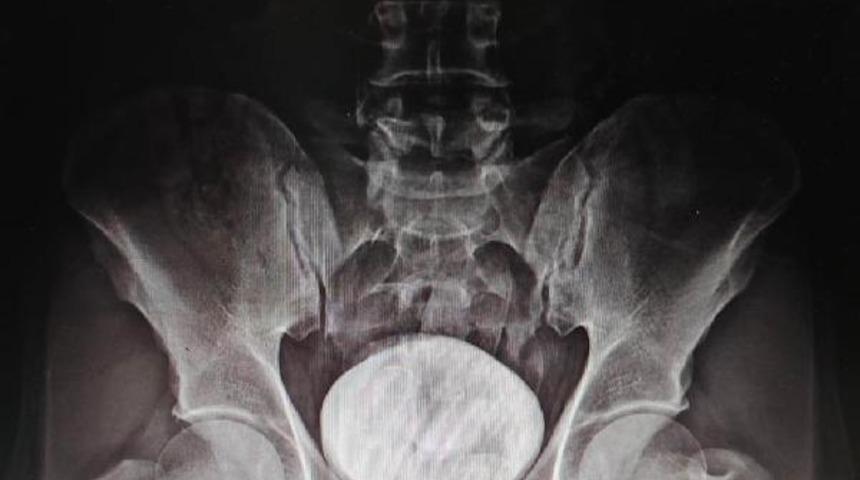

Kars Harakani Devlet Hastanesi’ne götürülen Tazehkand’ın çekilen röntgeninde, makatında uyuşturucu tespit edildi. Uyuşturucuyu doğal yollardan çıkaran Tazehkand, gözaltına alındı. Emniyetteki işlemlerinin ardından adliyeye sevk edilen şüpheli, çıkarıldığı hakimlikçe tutuklandı.